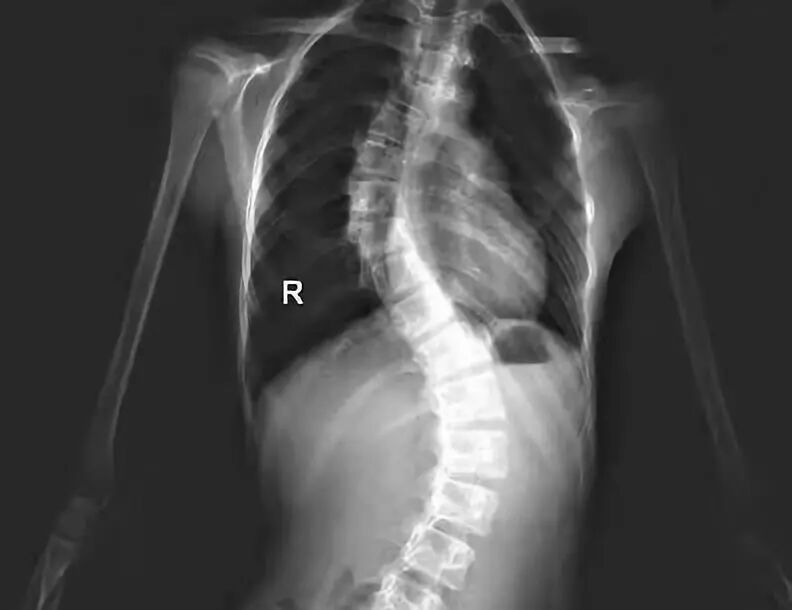

等到去医院检查,已经是严重的脊椎侧弯。